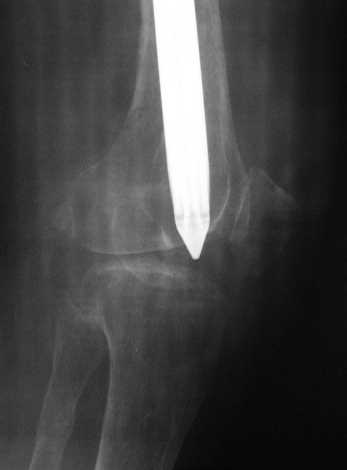

По просьбе коллег выношу на обсуждение следущий случай лечения перелома бедра, о дальнейшем лечении больной 48 лет с РПА. Анамнез: В 2005 году в ЦРБ - остеосинтез перелома бедра пластиной. В 2007 г. воспаление в ср. трети бедра и удаление пластины. Через 2 мес. - рефрактура и фиксация гвоздем "фикшн". Через 2 мес. после синтеза - свищ, "функционирующий" по настоящее время. Что делать? Если бы вопрос задавался лично мне, то я бы предложил удаление существующего фиксатора, санацию костномозгового канала, установку спейсера на тонком сплошном титановом гвозде с последущей заменой на полноценный сплошной титановый гвоздь.Правда, что делать с отверстием в колено, вернее как провести санацию так чтобы минимизировать риск распространения инфекции в коленный сустав, представляется не очень четко. Необходимую для обсуждения дополнительную информацию предоставлю по мере возможности.Спасибо.